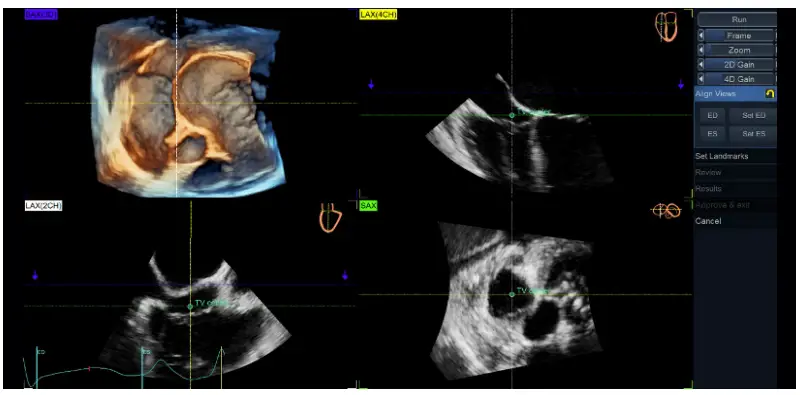

Align Views: - Place the TV center landmark at the center of TV annulus in both 4-chamber [LAX(4CH) – yellow] and the orthogonal view [LAX(2CH)) – white], as well as in the short-axis (SAX– green) view.

- Position the longitudinal axis of the RV to intersect the RV apex and the center of TV annulus in both 4CH and 2CH, as indicated in the miniature drawings shown in the right upper corner of each image

- The transversal green plane should be positioned at the TV annulus level, crossing approximately the leaflet hinges in each view (due to the saddle shape of the annulus, the plane position cannot be perfectly aligned with the 4 annulus points in both views simultaneously).

- The blue plane corresponds with the rendered SAX3D (upper left image) and it is generally recommended to be positioned on the ventricular side of the TV for TTE and on atrial side for TEE (Figure 3), close to the valve, to allow a proper visualization of the TV leaflet morphology and its spatial relationship with surrounding anatomic structures to facilitate the orientation of the user (Figure 4)

Figure 4. TV quad view showing the alignment of the views and planes with 4D Auto TVQ on a transthoracic TV data set